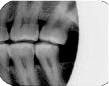

When the zygomatic process of the maxilla is superimposed on the roots of the maxillary molars (see Radiograph 4), another error occurs frequently with either technique. Too much vertical angulation will show this error in bisecting. Decreasing the vertical angulation by at least 10 degrees corrects it. With parallel technique, the key factor is improper placement of the film holder. Change the position of the film holder so the biting surface is flush with the occlusal and incisal surfaces.